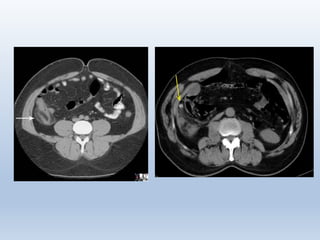

CT-Scan

(a) apendikogram tampak apendiks tidak terisi penuh oleh barium;

(b) CT-Scan (pada pasien yang sama) tampak apendiks dilatasi pada

daerah retrocecal.

MRI

(Kanan) Tampak apendikolith pada CT-Scan, (Kiri) MRI pada T1WI tampak

abses, tetapi apendikolith tidak tampak